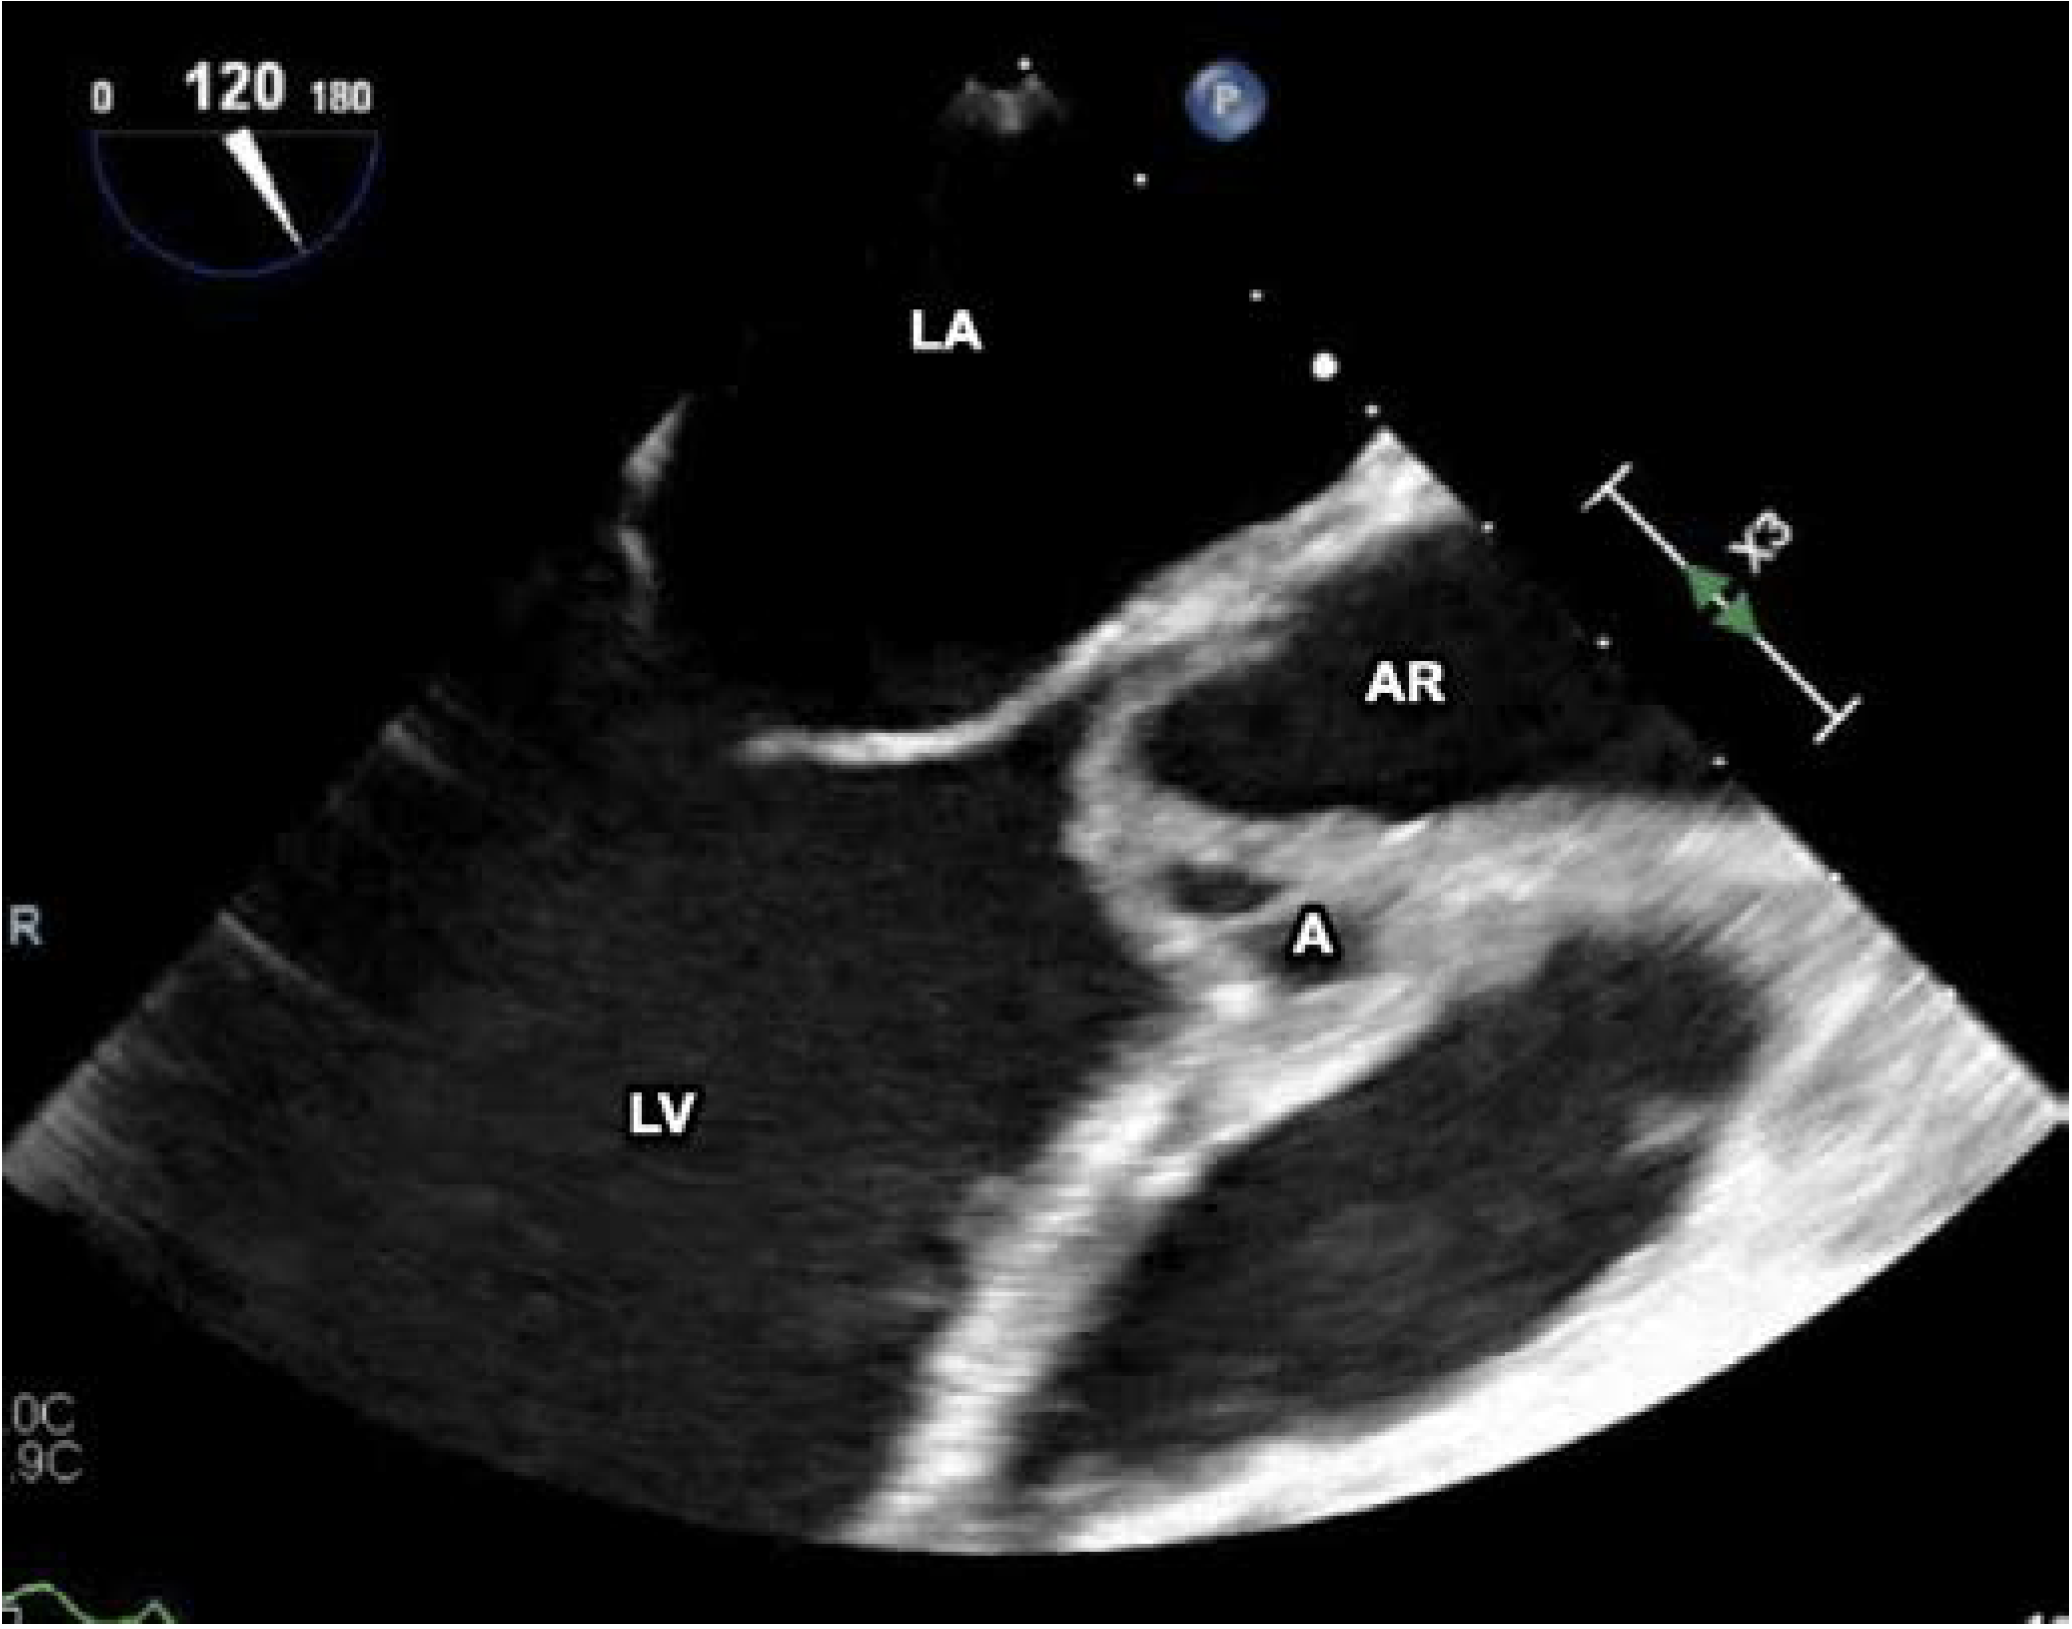

Initial surface echocardiography showed a bicuspid aortic valve with thickening of the right cusp and a small nodule suspicious for a vegetation, with mild eccentric aortic regurgitation. Transesophageal echocardiography (Figure 1) redemonstrated the bicuspid aortic valve, but with a large mobile echogenic mass measuring 1.6 cm on the right coronary cusp, with severe aortic regurgitation, an aortic root abscess (Figure 2), and evidence of right coronary leaflet prolapse into the left ventricle with associated perforation.

Figure 2. Transesophageal echocardiogram, showing the aortic root abscess. A—abscess; AR—aortic root; LV—left ventricle; LA—left atrium; V—vegetation.

In our case, the patient presented with acute endocarditis with a large mobile mass, associating with severe aortic regurgitation, an aortic root abscess and an associated perforation.